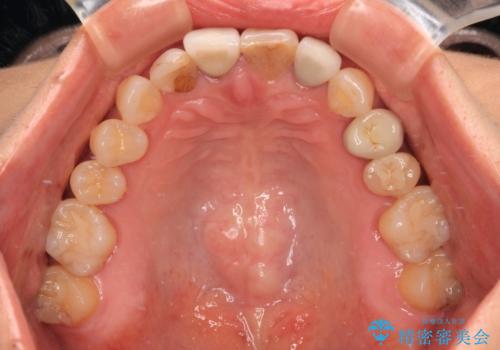

- 詰め物やクラウンで色合いが異なっている上顎前歯を気にして来院された患者様です。

長さや形を左右対称に整えたいとのことで、4歯をオールセラミッククラウンにて補綴治療を行うこととしました。